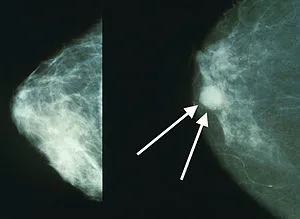

- Mammography: Being the most common detection test, in which an X-ray of the breast is conducted for detecting any lumps. This can even allow earlier detection and manual checkup. At this stage, detecting a lump is not always indicative of cancer, and requires further checkup such as via Ultrasound of MRI . Also for women under the age of 50, this test could fall short on detecting tumors due to dense breast tissues in younger women.

Screening recommendations in line with above statement are as follows, as found under wikipedia (source 1):

For the average woman, the U.S. Preventive Services Task Force recommends mammography every two years in women between the ages of 50 and 74, the Council of Europe recommends mammography between 50 and 69 with most programs using a 2-year frequency, and in Canada screening is recommended between the ages of 50 and 74 at a frequency of 2 to 3 years